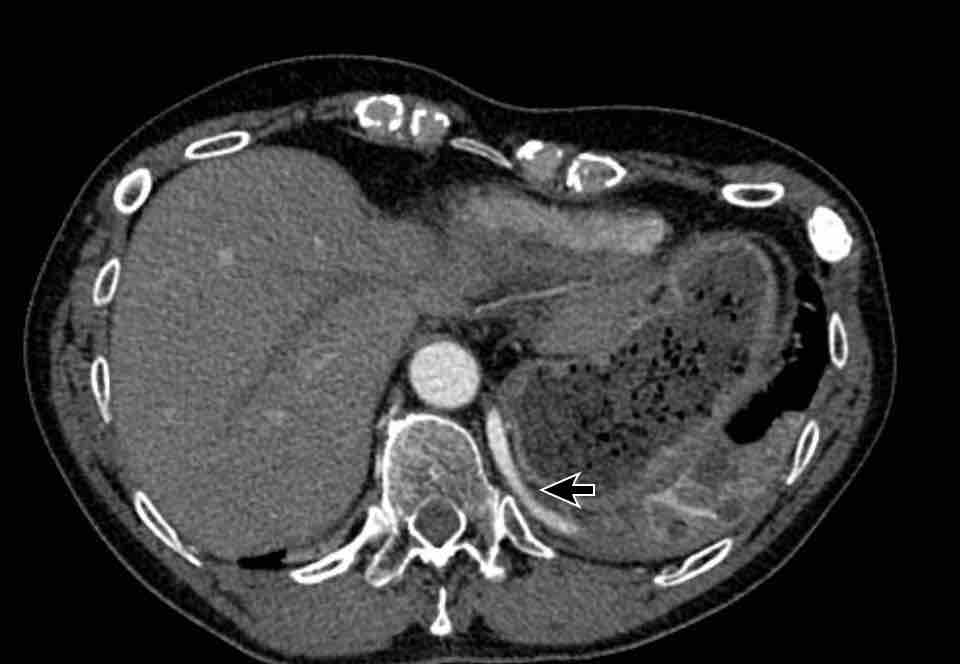

Hình ảnh

Bệnh nhân này được lên kế hoạch cắt thùy trên phải do ung thư phổi và bất thường mạch máu này ban đầu đã bị bỏ sót trên hình ảnh CT.

Những hệ quả trong phẫu thuật của bất thường như vậy nhấn mạnh tầm quan trọng của việc không bỏ sót các biến thể này.

PAPVR bên trái phát hiện tình cờ với dẫn lưu trên tim của máu từ thùy trên trái vào tĩnh mạch tay đầu trái (các mũi tên).